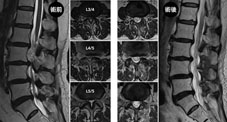

治療退化性椎管狹窄其實是「雙通道脊椎內視鏡微創椎管減壓術」的最大強項,只要透過兩個小小的傷口和極小的椎板開窗,就可以把內視鏡深入到椎管深處,進行徹底的減壓,就好像隧道工程一樣,把過於老舊壅塞的隧道拓寬,但卻不破壞隧道的結構,安全又有效(如圖三);而且由於骨性結構破壞很小,所以不需要打鋼釘來進行椎間融合,也讓腰椎原有的活動功能得以保留,避免了許多的後遺症。減壓手術時的最大利器就是從日本進口的「微創高速電動骨鑽」,因為器械又細又長,所以可以透過UBE的小傷口以高達每秒八萬轉的超高轉速切削骨刺,我們所選用的鑽石磨頭可以兼顧效率與安全,大幅減少神經損傷的風險。截至2022年7月,我們已經累積了超過800例的UBE手術經驗,在我們的努力下,已經將神經損傷的機率降低到小於百分之0.25,遠遠低於世界頂尖醫學中心的水準(百分之3-5),可以說是革命性的成果。

圖三、UBE減壓手術就像隧道拓寬工程一樣,將老舊狹的隧道拓寬,但不影響隧道原來

的結構;也可以依序進行多椎節的手術,有效達到減壓的目的,同時避免傳統手術的後遺症